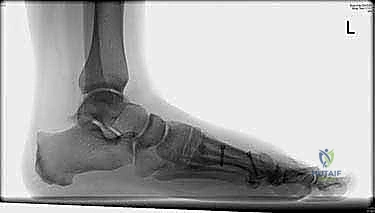

Before we even consider making an incision, our blueprint for this procedure begins with meticulous preoperative planning. We've thoroughly evaluated the patient's weight-bearing anteroposterior (AP) and lateral radiographs of the foot. These images are critical for assessing several key parameters:

- Intermetatarsal Angle (IMA): The primary indication for a Scarf osteotomy is typically a symptomatic hallux valgus with an IMA of less than 20 degrees. We're looking for a stable first metatarsocuneiform joint here; instability might push us towards a fusion.

- Hallux Valgus Angle (HVA): This measures the lateral deviation of the great toe.

- Distal Metatarsal Articular Angle (DMAA): This assesses the orientation of the articular surface of the first metatarsal head. An abnormal DMAA, especially in juvenile hallux valgus, can be corrected effectively with a Scarf.

- Interphalangeal Angle (IPA): If this angle is significantly elevated, it may indicate the need for a concurrent proximal phalangeal osteotomy, such as an Akin osteotomy, to achieve complete correction. We've templated for this possibility.

- Metatarsal Length: We assess for any relative shortening or lengthening that might be required. The Scarf is unique in its ability to allow for shortening, lengthening, rotation, displacement, or even plantarization of the first metatarsal head.

- Joint Congruency: We note the congruency of the first metatarsophalangeal (MTP) joint. While the Scarf is excellent for arthritic hallux valgus not severe enough for a fusion, severe incongruity or advanced arthritis might warrant a different approach.

- Osteophytes: Presence and size of any dorsal or medial osteophytes.

- Medial Eminence: The size of the bony medial eminence, or "bunion," which we will resect.

- Sesamoid Position: The position and condition of the sesamoids under the first metatarsal head. Lateral subluxation is a hallmark of hallux valgus, and their reduction is a key indicator of successful correction.

Today's patient presents with symptomatic hallux valgus, an IMA of 16 degrees, and moderate lateral sesamoid subluxation, making the Scarf osteotomy an ideal choice.